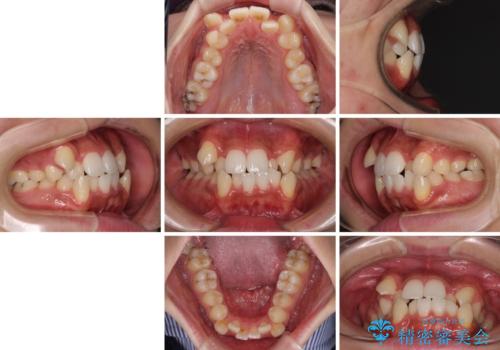

上下の八重歯とクロスバイト ワイヤー装置での抜歯矯正

- 八重歯とクロスバイトを気にして来院された患者様です。

上下ともに八重歯が顕著であり、前歯のクロスバイトがあったため、上下左右の第一小臼歯4本を抜歯し、ワイヤー装置での抜歯矯正を行うこととしました。